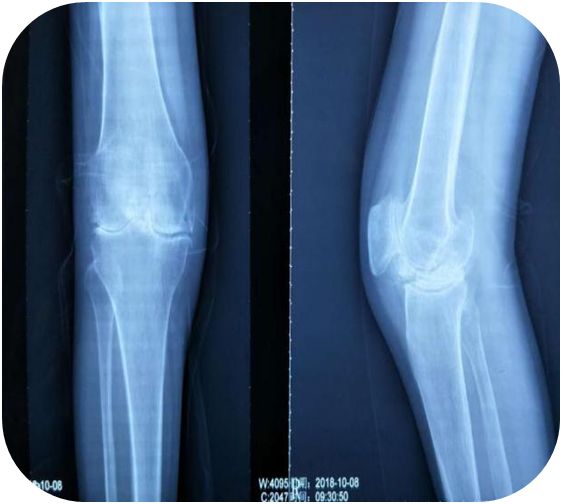

患者出院后也一直门诊坚持治疗,每月2次,期间行关节腔注射玻璃酸钠2次润滑关节,至2019年5月予患者复查右膝关节X片,患者膝关节间隙较前明显清晰,患者膝关节疼痛明显减轻,基本无疼痛,行走时感少许酸软无力,膝关节活动度较前明显增大,从原先腘窝下距离床面三拳明显减少到一拳,后患者陆续又行双肩、双肘关节小针刀松解术,疼痛也得到明显改善。

患者治疗前后膝关节X线片对比